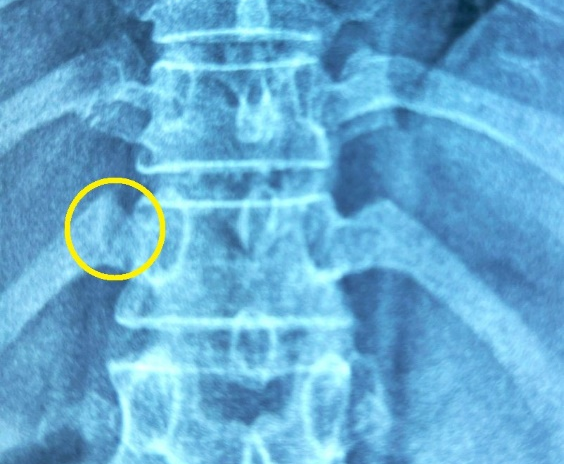

Vị trí xương sườn của bệnh nhân bị gãy sau khi đi ấn huyệt, bẻ khớp - Ảnh: Bác sĩ cung cấp

Ông A. được xử trí laser giảm đau, uống thuốc giảm đau tại chỗ. Sau 15 phút, ông có thể ngồi dậy, bớt đau và ngồi được xe lăn. Ông được chụp thêm X-quang, kết quả cho thấy bị gãy xương sườn 12, phạm khớp sườn cột sống.